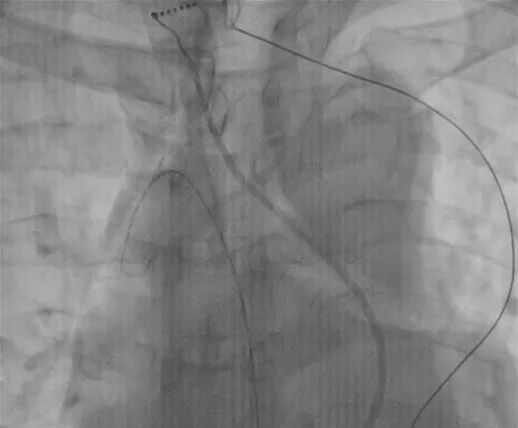

▲导丝由股静脉进入后跨过奇静脉进入右心房

更棘手的是,术中团队发现患者存在下腔静脉缺如,血液需通过扩张的奇静脉回流至右心房,同时左侧颈内静脉完全缺失,双重血管变异直接导致常规经血管入路受阻,房间隔穿刺这一射频消融术的关键步骤更是难上加难。